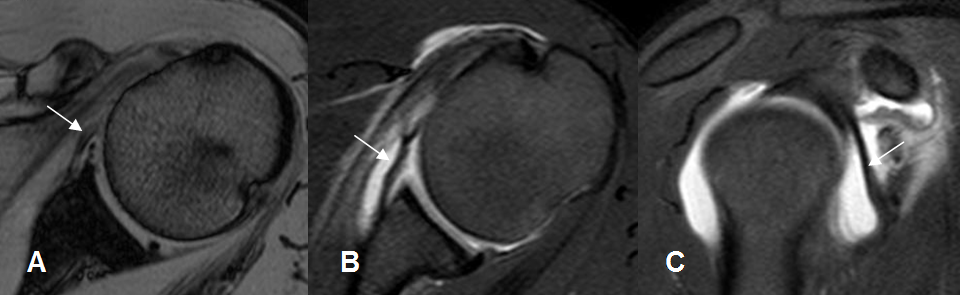

Fig 14. Tendón del subescapular normal.

A: RM axial en FFE y B: RM coronal en T1. Inserción en la tuberosidad menor. Su relación

con la apófisis coracoides (Flecha gruesa), ayuda a diferenciarlo del redondo menor.

Fig 15. Tendón del redondo menor normal.

RM coronal en T1. Inserción en la tuberosidad mayor.

Fig 16. Tendón de la cabeza larga del bíceps normal.

A: RM axial en FFE y B: RM coronal en STIR. Origen del tendón a nivel supraglenoideo y después ocupa la corredera bicipital.

Fig 17. Tendones normales del manguito rotador.

RM sagital en T2. SE: Supraespinoso. IE: Infraespinoso. SB: Subescapular. RM: Redondo menor. BI: Cabeza larga del bíceps.